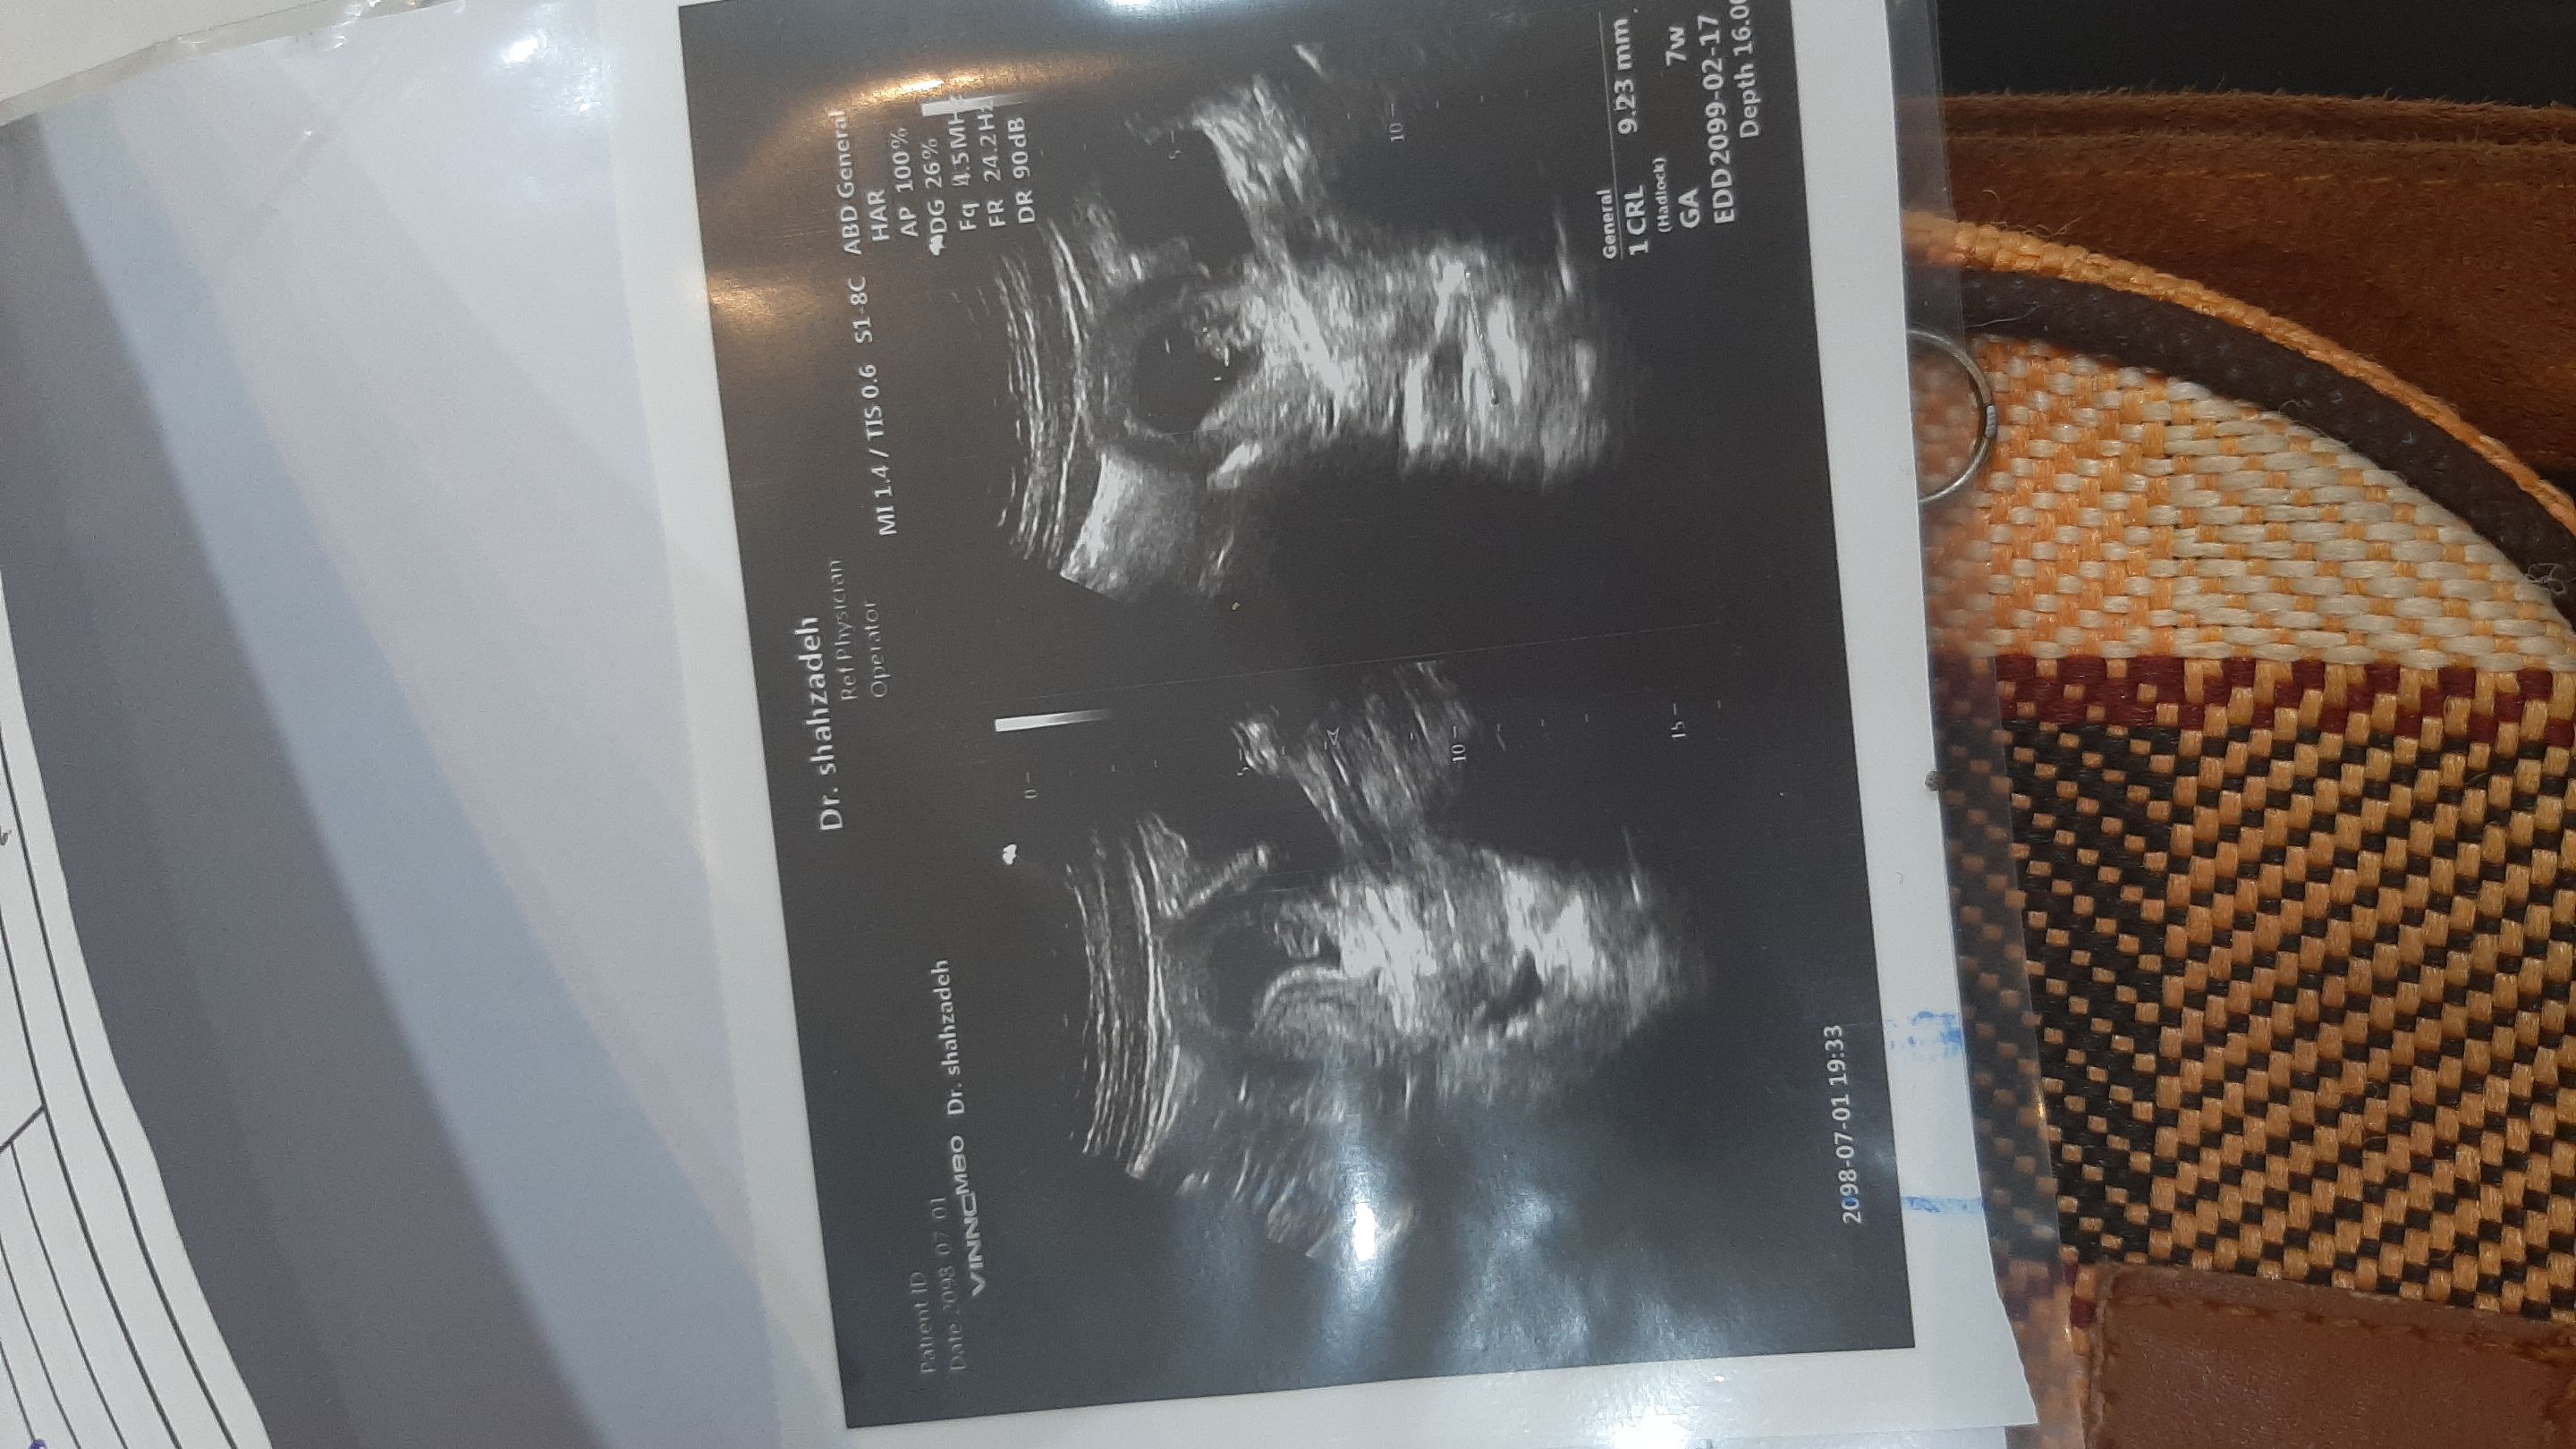

ناهیدبانوو۷۰ عضویت: 1398/05/25 تعداد پست: 7452 سونو هفت هفتگی رو بفرست عزیزم برای منم بگو بیزحمت شدی قلبُ تنُ روحم 💍💕

ناهیدبانوو۷۰ عضویت: 1398/05/25 تعداد پست: 7452 عکس سونو بفرستین عزیز رفتم سونو فهمیدم پسره😄حتی جشنم گرفتیم😄💙 شدی قلبُ تنُ روحم 💍💕